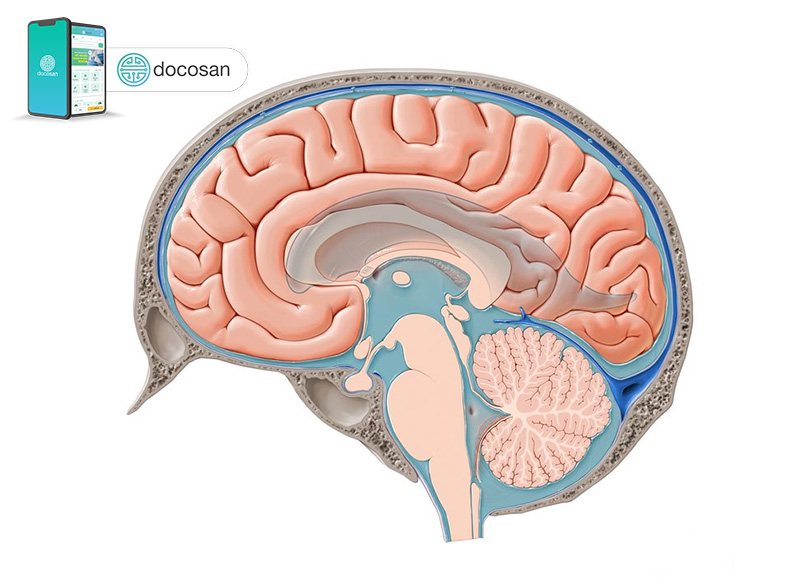

Dịch não tủy là gì?

Hệ thống thần kinh trung ương bao gồm não và tuỷ sống, đây là trung tâm kiểm soát và điều phối mọi hoạt động trong cơ thể chúng ta, bao gồm cả chuyển động của cơ bắp, chức năng của các cơ quan và thậm chí cả những suy nghĩ phức tạp.

Dịch não tủy (Cerebrospinal Fluid – CSF) là một chất lỏng trong suốt, không màu xung quanh não và tuỷ sống. Dịch não tuỷ đóng vai trò là một tấm đệm, chống lại các tác động mang tính đột ngột hoặc dễ gây chấn thương lên não/tủy sống. Dịch não tủy cũng lưu thông giúp loại bỏ các chất thải từ não, tạo môi trường thuận lợi để hệ thống thần kinh trung ương hoạt động tốt nhất.